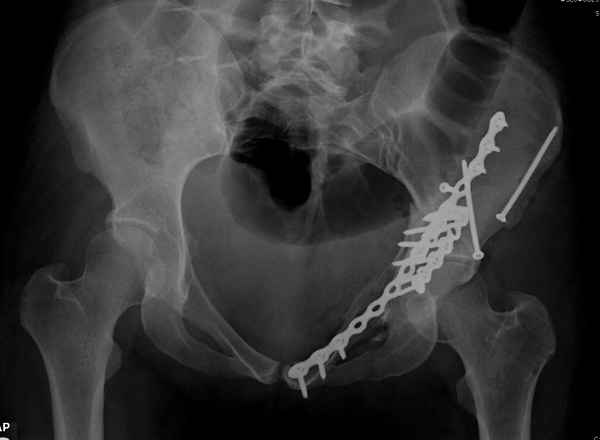

По-моему, надо готовить больного к будущей артропластике, но без опоры на задний столб невозможно удержать протез. Опорная конструкция (кольца и т.д.) должны иметь опору, и поэтому мы бы сделали реостеосинтез задним доступом. При надобности остеотомия и рутинная фиксация с межколонными винтами.

Здесь несколько вариантов двухколонных свежих переломов, которые были оперированы из одного-заднего, а также из двух: переднего и заднего доступов.